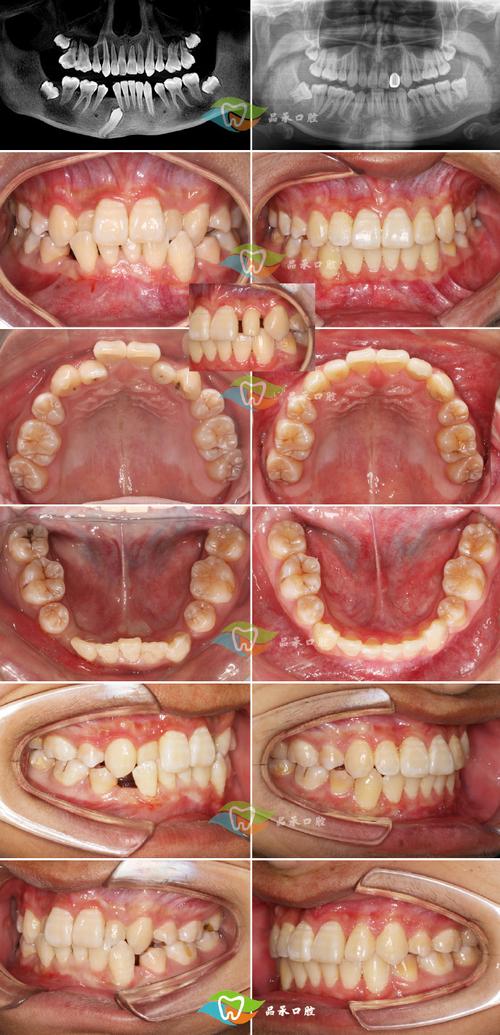

(图片来源网络,侵删)- 儿童和青少年: 是矫正的主力军,尤其在有保险覆盖的国家。